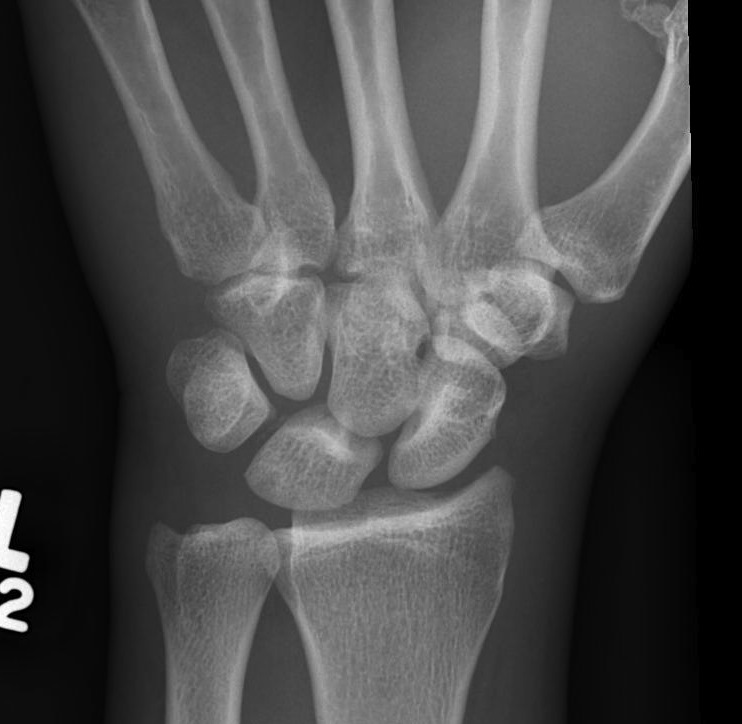

X-ray

Disruption of Gilula's 3 smooth carpal arcs

Progressive Injury

1. Capitate dorsal

- lunate remains with radius

- lunate looks triangular on AP

2. Lunate dislocates

- usually volar